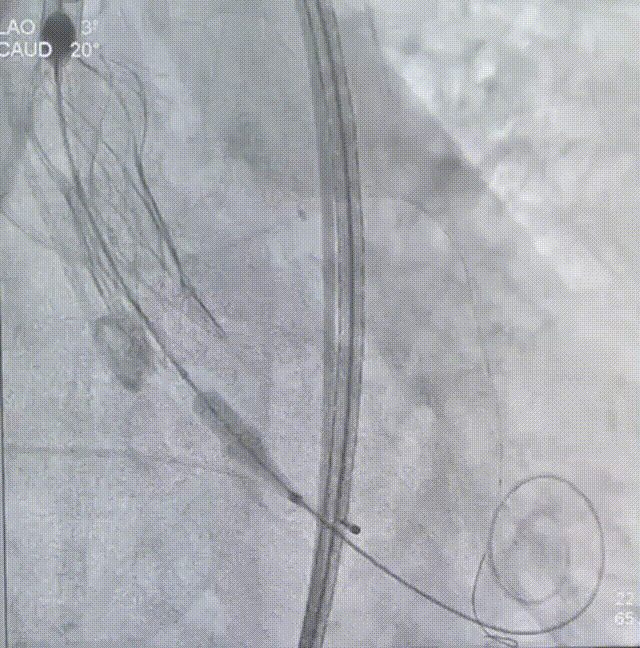

22mm球囊预扩

瓣膜定位

瓣膜释放至75%

瓣膜脱钩

瓣膜完全释放

22mm球囊后扩

完成植入